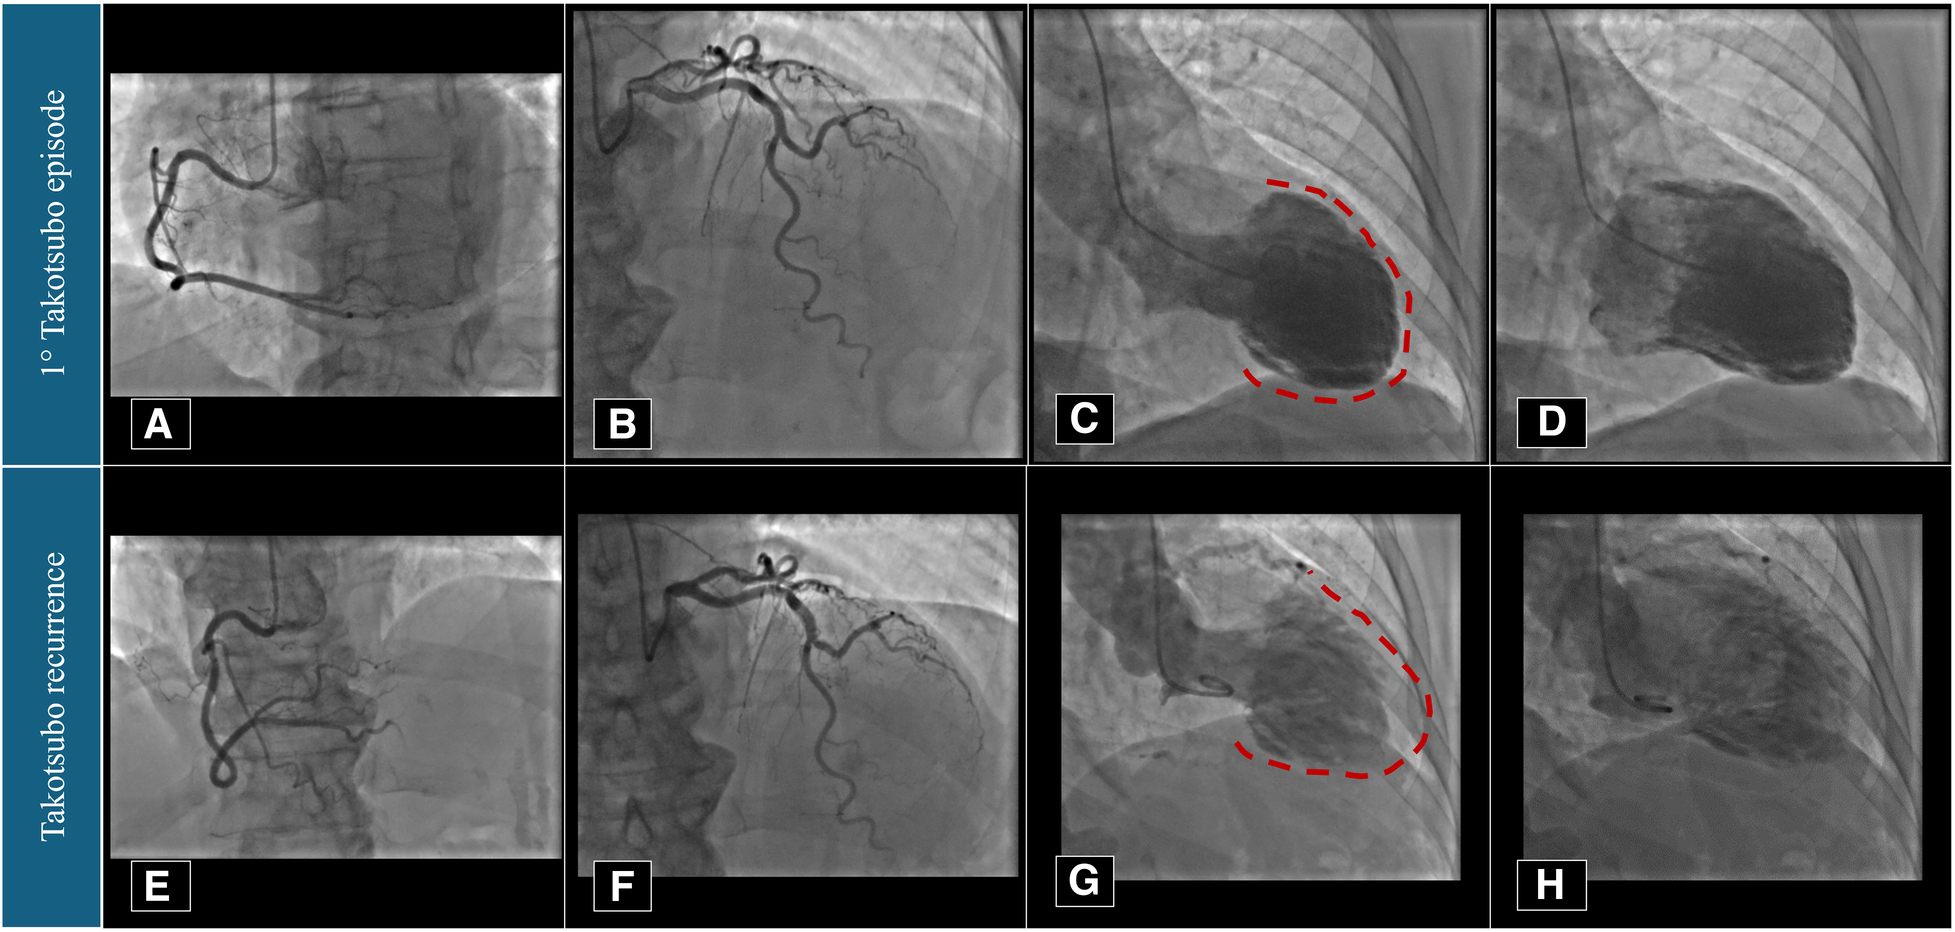

Figure 2

Coronary angiography and left ventriculography imaging performed in 2021 (A–D) and 2023 (E–H). Red dotted lines underline the apical akinesia during left ventricular systole.

The patient is a 74-year-old woman with type 2 diabetes mellitus, hypercholesterolaemia, mild overweight (25.7 Kg/m2), and a remote undocumented history of myocardial infarction in the infero-lateral wall treated by intravenous fibrinolysis. Back then, no coronary artery disease was found at angiography. More recently, in 2021, she was admitted to hospital with a diagnosis of TTS. In that case, she complained of new onset chest pain following an argument on the phone. The 12-lead ECG showed negative T-waves in the infero-lateral leads (Figure 1A). The coronary angiography documented tortuous epicardial coronary arteries, free from significant lesions, with diffuse slow flow (Figures 2A,B). Hyperkinesia of the basal segments, akinesia of the middle and apical segments, and ejection fraction (EF) of 35% were seen at left ventriculography (Figures 2C,D). White blood cell count was 6,690/mmc (URL 10,000/mmc), peak plasma level of high-sensitive troponin-T was 216 ng/L (female gender URL <10), whereas urinary metanephrines were within normal limits. On day 5, a cardiac magnetic resonance (CMR) confirmed the diagnosis (Figures 3A–E) showing in addition the presence of a small intraventricular thrombotic formation (15 × 8 mm) for which oral anticoagulant therapy was given. Discharge therapy included an angiotensin-converting enzyme (ACE) inhibitor. Oral beta blocker was not prescribed in consideration of the occurrence of significant bradycardia on that drug. The clinical course was uncomplicated and, 6 months after the event, a planned CMR found complete functional recovery of the left ventricle, oedema reduction, disappearance of the intraventricular thrombus, subendocardial late gadolinium-enhancement (LGE) at the basal inferolateral wall level (Figures 3F–J) as a result of remote necrosis. Oral anticoagulation was stopped.

In early 2023, the patient arrived at the Emergency Room complaining of fatigue and chest pain. Since the ECG showed slight QRS widening, left anterior hemiblock, and ST-segment elevation in the lateral leads (Figure 1B), the patient underwent an immediate invasive angiography, which excluded again the presence of coronary artery stenosis and showed the apical ballooning pattern of the left ventricle, as in the previous episode (Figures 2E–H). The diagnosis was recurrent TTS. Research of obvious physical or emotional stress was negative. The only relevant finding was a positive routine swab test for severe acute respiratory syndrome coronavirus-2 (SARS-COV-2), in the absence of fever or respiratory symptoms. The hospital stay was prolonged due to transient QT-segment elongation, but no complications occurred. In consideration of the paucity of data about TTS relapse, the patient performed a third CMR. The imaging pattern was similar to that observed 2 years before: extended akinesia at the level of the middle and apical segments, which appeared diffusely oedematous in the STIR sequences; stable subendocardial LGE with ischemic pattern at the basal infero-lateral wall (Figures 3K–O). We repeated the urinary metanephrine assay which demonstrated a slight, but not significant, increase in normetanephrine. WBC count was 5,450/mmc (URL 10,000/mmc), plasmatic interleukin-6 title was 44.7 pg/ml (URL < 5.9), while high-sensitive troponin-T peak was 386 ng/L (female gender URL <10).